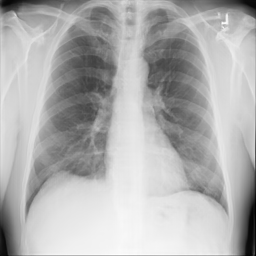

We used the NIH Chest X-ray 14 [73] dataset to conduct our experiments. This dataset consists of labeled chest X-ray images, from over unique patients corresponding to 14 common thoracic disease types, including atelectasis, cardiomegaly, effusion, infiltration, mass, nodule, pneumonia, pneumothorax, consolidation, edema, emphysema, fibrosis, pleural thickening, and hernia. The dataset is divided into training, validation, and testing sets, containing , . and images, respectively444We followed the dataset splits in https://github.com/zoogzog/chexnet/tree/master/dataset. Our experiments were designed to examine and compare four training methods:

Figure 7 samples real and GAN-generated images. The first column presents real images, the second column GAN-generated unsupervised, and the third GAN-generated supervised. The GAN-generated images may successfully fool our colleagues with no medical knowledge. However, as reported in [63], the GAN-generated labeled chest X-ray images must be screened by a team of radiologists to remove erroneous data (with respect to diagnosis knowledge). Without domain knowledge, incorrectly labeled images may be introduced by GANs into the training pool, which would degrade classification accuracy.

| Real | GAN unsupervised | GAN supervised |